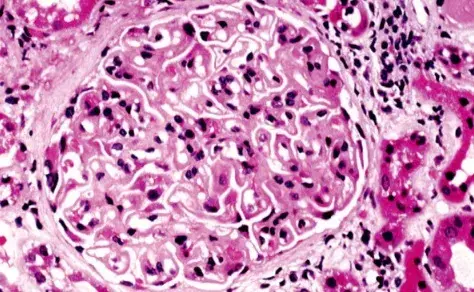

Es posible identificar un glomérulo con rotura de la membrana basal glomerular, con crecimiento celular en el espacio de Bowman (flecha blanca), células gigantes multinucleadas (estrella) y ruptura de la cápsula de Bowman (flecha negra) (tinción PAS; 400×). PAS, ácido periódico-Schiff.

La biopsia renal reveló GN (glomerulonefritis) crescéntica necrotizante difusa sin hipercelularidad endocapilar. Algunos raros glomérulos contenían células gigantes multinucleadas.

La evaluación de la microscopía de luz puede ayudar en la diferenciación entre casos de **GN por anti-MBG** y casos de **GN-ANCA**, ya que en la GN por anti-MBG no se observa hipercelularidad endocapilar y se puede identificar la presencia de células gigantes multinucleadas. Estas células gigantes multinucleadas resultan de la naturaleza explosiva y la rápida destrucción de los glomérulos observada en la anti-MBG.

Por lo tanto, la presencia de lesiones crescénticas temporalmente similares y células gigantes multinucleadas en la microscopía de luz (MO) puede ayudar en el diagnóstico temprano."